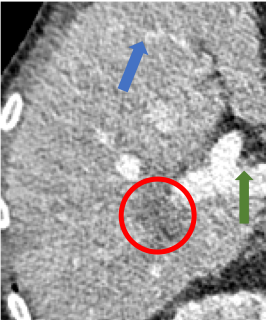

To demonstrate the effectiveness of the proposed network, we perform the qualitative comparisons over three representative abdominal images presented in Figs. 3, 5 and 7. For better evaluations of the image quality with different denoising models, zoomed regions-of-interest (ROIs) are marked by red rectangles and shown in Figs. 4, 6 and 8 respectively. Note that all results from different denoising models focus on two aspects: content restoration and noise-reduction. All CT images in axial view are displayed in the angiography window [-160, 240]HU.

The real NDCT images and corresponding LDCT images are presented in Figs. 3a and 3b. As observed, there are distinctions between ground truth (NDCT) images and LDCT images. Figs. 3a and 7a show the lesions/metastasis. Fig. 5a presents focal fatty sparing/focal fat. In Figs. 4a, 6a and 8a, these lesions can be clearly observed in NDCT images; in contrast, from Figs. 4b, 6b, and 8b, it can be seen that the original LDCT image is noisy, and lacks structural features for task-based clinical diagnosis. All adopted denoising models suppress noise to some extent.

Indeed, the images of WGAN-VGG[37], as shown in Fig. 3j, exhibit better visual quality with respect to more details and share structural details similar to NDCT images according to human perceptual evaluations. However, Figs. 4j (marked by the red circle) and 6j (marked by the green circle) suggest that it may severely distort the original structural information. A possible reason is that the VGG network [47] is a pre-trained deep CNN network based on natural images, and the structural information and contents of natural images are different from medical images.

Compared with WGAN and WGAN-VGG, our proposed SMGAN-3D, as shown in Figs. 4l (marked by the red circle) and 6l (marked by the green circle), can more clearly visualize the metastasis and better preserve of the portal vein.

To validate the robustness of DL-based methods, we compared our method with the image space denoising method. Figs. 4h and 6h show that BM3D blurs the low-contrast lesion marked by the red circle and smooths specific features marked by the blue arrow. In contrast, SMGAN-3D exhibits better on the low-contrast lesion and yields sharper features as shown in Figs. 4l and 6l.